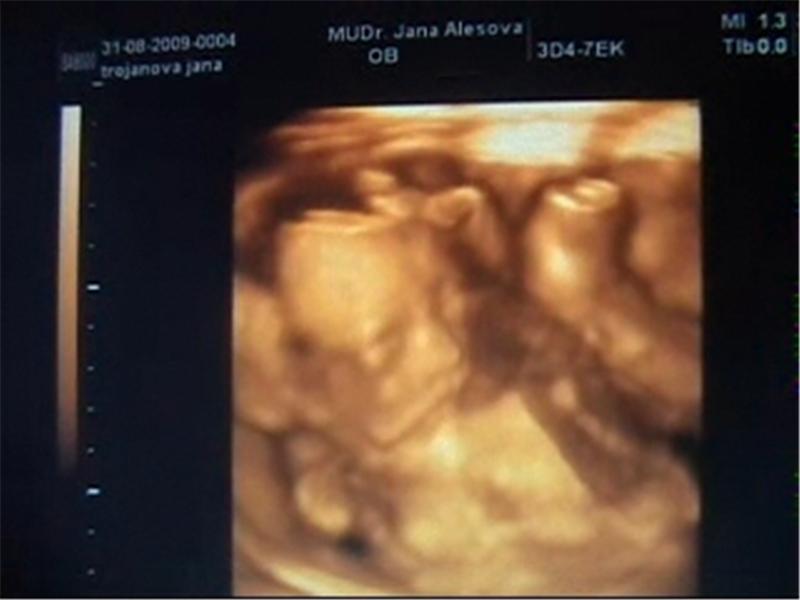

Moje Nikolka